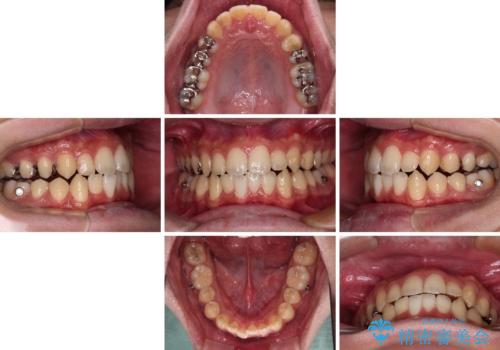

前歯のクロスバイト インビザラインによる矯正治療

- 上下のクロスバイトと前歯のデコボコを気にして来院された患者様です。

インビザラインを用い、IPR(歯と歯の間を削る)と歯列全体を拡大させることで、歯並びを整えていくこととしました。

インビザライン特有の、治療後半に奥歯が咬み合わないという事象が長引きました。

咬み合わないときの対処方法は色々とありますが、ゴムかけなどを活用して噛めるようにしました。